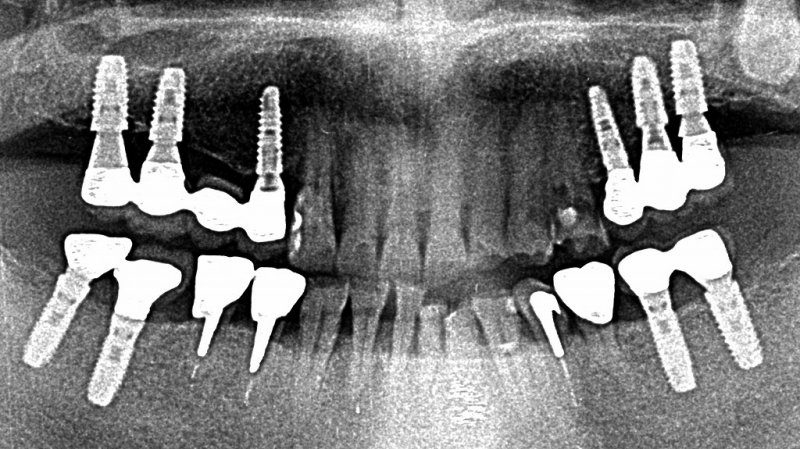

多数歯欠損症例

複数歯にわたる欠損では、インプラント本数、埋入位置、咬合力分散を含めた全顎的な設計が求められ、診断と治療計画の難易度が高くなります。

当院では、骨量不足、多数歯欠損、全顎再建など、一般的には難症例とされるケースに対しても、段階的かつ安全性を重視した治療を行っています。

骨造成と再生療法を併用した多数本埋入症例

上顎洞挙上術を伴う広範囲インプラント治療

いずれの症例も、精密診断と適切な治療計画により、機能性・審美性の回復を実現しています。